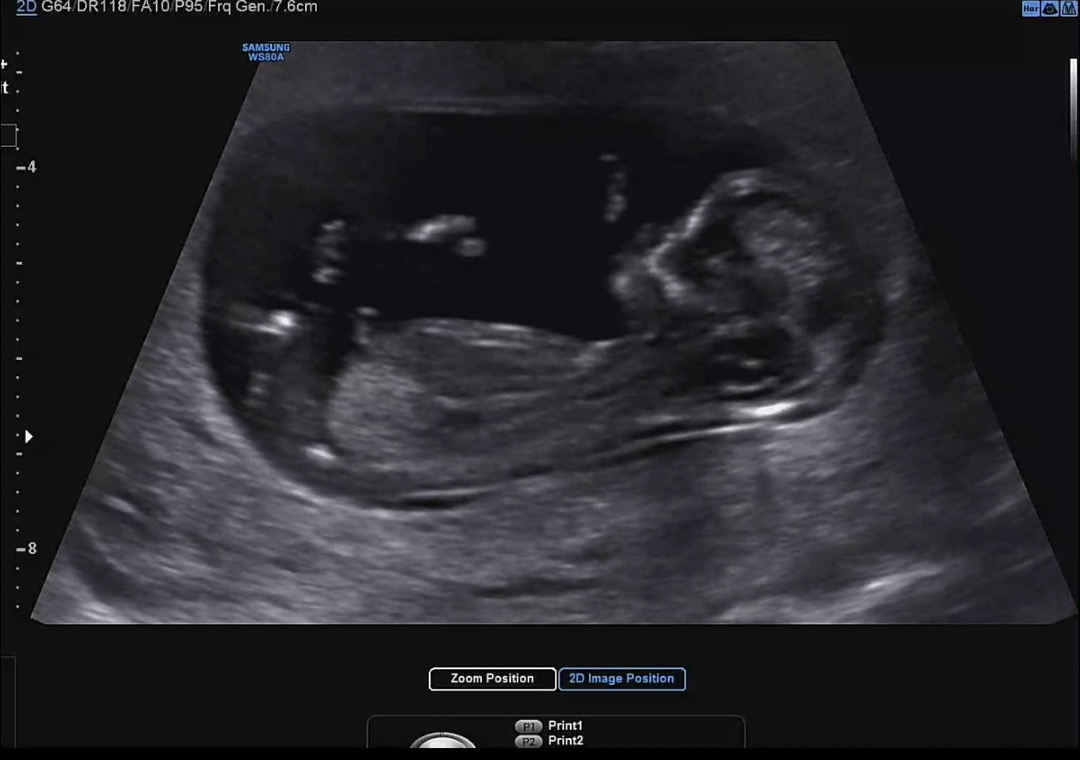

12주 각도법 봐주세요☺️

12주 0일차 1차 기형아 검사 방금 받았는데 성별이 너무 궁금해요! 아들일까요 딸일까요?

딸같아요 반전가능성은있어요